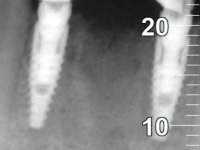

Após estudo imagiológico foi planificada a colocação de dois implantes de 3.3 mm de diâmetro e 10 mm de comprimento. No dia da cirurgia foram extraídos os dentes 42 e 32 e removido o implante. Os implantes foram colocados na zona dos alvéolos tendo o cuidado de lingualizar um pouco o seu posicionamento. Foi feita uma impressão pela técnica de moldeira aberta com o retalho aberto para a confeção da ponte provisória imediata. Enquanto a impressão foi para o laboratório, foram colocados parafusos de cicatrização altos e feita a sutura da ferida cirúrgica. A paciente esperou 2 horas na sala de espera enquanto no laboratório era confecionada a ponte provisória. A ponte provisória imediata aparafusada foi colocada e o seu assentamento controlado imagiologicmente. Passados 3 meses foi realizada a impressão definitiva com uma técnica de moldeira aberta. Nessa consulta aproveitamos para polir a ponte provisória com taças de borracha para que os tecidos moles pudessem maturar em melhores condições. Foi feita a recolha de informação para caracterizar da melhor forma a estrutura monolítica em Zr. Foram utilizadas guias de cor para a cerâmica de tonalidade coronária e gengival. No laboratório foi confecionada uma ponte em Zr. aparafusada que foi cuidadosamente caracterizada. Após aprovação pela paciente foi colocada definitivamente em boca. O aperto foi feito com uma chave dinâmica com 35 N de torque. Os orifícios foram tapados com teflon e obturados com resina composta.